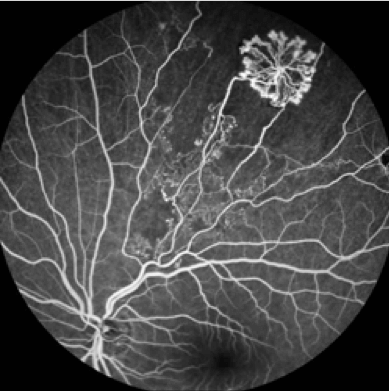

A Fluorescein Angiogram (FA) or Intravenous Fluorescein Angiogram is a diagnostic test that is used to study the retinal blood vessels and circulation of blood in the retina. Fluorescein Angiography is a valuable test that provides valuable information about many eye diseases including Diabetic Retinopathy, Macular Degeneration, Retinal Vascular Disease such as Retinal Artery Occlusion and Retinal Vein Occlusion as well as other types of Macular Disease.

Prior to beginning the study, your pupils will be dilated. The Fluorescein Angiography study is performed by injecting a sodium-based dye, called Sodium Fluorescein, into an arm vein. During the injection, there can be a warm feeling or a hot flush. This only lasts seconds and then disappears. The dye appears in the retinal blood vessels within about 10-15 seconds. As the dye travels through the retinal blood vessels, an ophthalmic photographer or technician takes a series of photographs of the Retina with a special high-speed retinal camera. Capturing the photographs takes about 6-10 minutes.

If there are any abnormalities, the dye will usually reveal them by leaking, staining or by its inability to get through blocked blood vessels. Eyecare Medical Group doctors will look for any abnormalities by identifying areas that exhibit hypofluorescence (darkness) or hyperfluorescence (brightness). These are descriptive terms that refer to the relative brightness of fluorescence in comparison with a normal retinal angiography study. Although statistically very rare, mild to severe adverse reactions to the intravenous dye have been reported. Our staff will review the potential risks and complications of Fluorescein Angiography with you and answer all of your questions prior to your study.